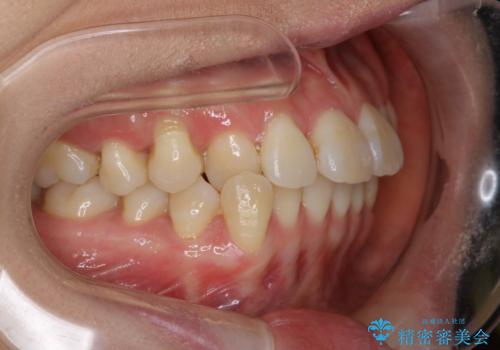

- 前歯のがたつきが気になるとご相談にいらした方です。右側前歯部のクロスバイトの他、左側にもシザーズバイトが認められたため、インビザラインにて治療を行いました。出産直後のため、ご自身の時間がなかなか取れないとの事で、最小限の来院回数で治療を勧められるように計画しました。

患者様ご自身で使用時間をしっかり管理して頂くことを条件に、最低限の来院回数で治療を進めていきました。20時間以上の使用を厳守して頂けたことで、少ない来院回数にて治療を終了することが出来ました。前よりも噛みやすくなったと大変喜んでいただけました。